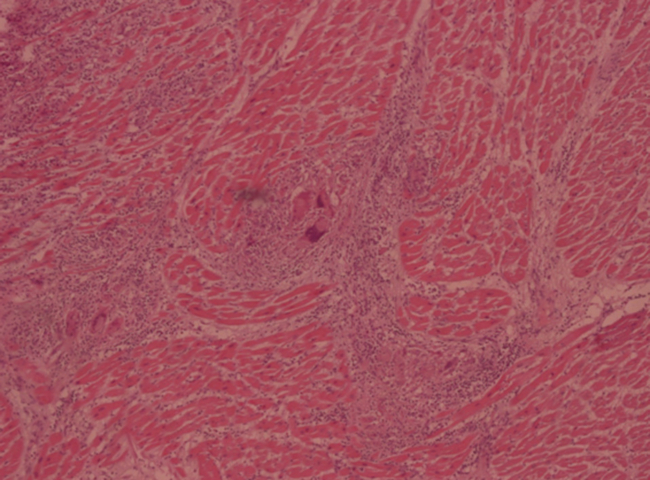

El estudio histológico del corazón mostró un infiltrado extenso de tipo linfoplasmocitario con eosinófilos, histiocitos y células gigantes multinucleadas con citoplasma de aspecto “apolillado”, otras células de citoplasma esmerilado (cuerpos de Schauman), otros de aspecto estrellado (cuerpos asteroides) que en sectores se encontraban circunscribiendo granulomas no caseificantes de tipo sarcoidal, que comprometía pericardio, miocardio ventricular, septal, músculos papilares y endocardio, que disecaba las fibras musculares con áreas de fibrosis . Se observó en sectores picnosis nuclear y homogenización de la fibra miocárdica. (Figuras 1 y 2)

Histología del tejido miocárdico.